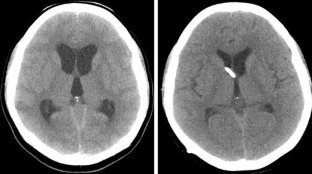

Fig. 1

Fig. 2

Fig. 3

Fig. 4